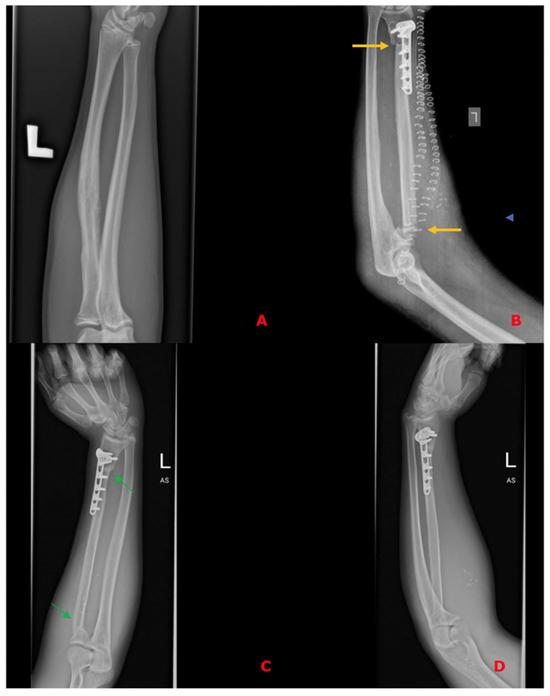

In all of the patients included, a fibula free flap (FFF) was applied to carry out the reconstruction with possible modifications regarding the harvest of the flap when the metaphysis was involved. The intraoperative photographs of the FFF harvest are presented in Figure 2. Most commonly, a FFF was applied to reconstruct the diaphyseal part of the long bone. In cases of the short stump of the long bone after resection part, to prevent arthrodesis, due to the lack of technical possibility of stabilizing the proximal part of the radius using a titanium plate, stabilization with non-dissolvable sutures was used by drilling holes within the proximal part of the fibula, with subsequent thread insertion through the holes created and suture fixation through the cortical layer of the remaining proximal stump of the radius (Figure 3). When the resection was not limited only to the shaft of the long bone but also included partially the proximal metaphysis of the radius, the FFF was harvested with the head of the fibula in a typical manner. During the harvest of the fibular head, the deep peroneal nerve was carefully dissected off the bone and spared, which is the crucial point for mitigating donor-site morbidity. The fibular head replaced the function of the head of the radius at the humero-radial joint and was inserted directly into the spared annular ligament of the radius, maintaining the functionality/mobility of the limb and avoiding the endoprosthesis of the humeroradial joint at the same time (Figure 4). This solution was possible due to the sparing of the annular ligament, which ensured adequate stabilization of the fibular head.

In the other case presented in Figure 3 due to the lack of technical possibility of stabilizing the proximal part of the FFF using a titanium plate, stabilization with non-dissolvable sutures was used by drilling holes within the proximal part of the fibula, with subsequent thread insertion through the holes created and suture-fixation through the cortical layer of the remaining proximal stump of the radius. This solution also allowed for preventing arthrodesis.

Figure 3. (A)—Preoperative X-ray of histopathologically confirmed Ewing Sarcoma of the left radius without metaphysis involvement; (B)—X-ray on the 1st postoperative day after resection of a specimen and reconstruction of the defect using a free fibula flap, confirming the proper axis of the reconstructed bone, bone contact points (yellow arrows), and correct positioning of the free flap. Due to the lack of technical possibility of stabilizing the proximal part using a titanium plate, stabilization with non-dissolvable sutures was used by drilling holes within the proximal part of the fibula, with subsequent thread insertion through the holes created and suture fixation through the cortical layer of the remaining proximal stump of the radius; (C,D)—Follow-up X-rays in the 14th postoperative month with visible bone union—osteointegration of the flap (green arrows) and the restored correct axis of the upper limb.